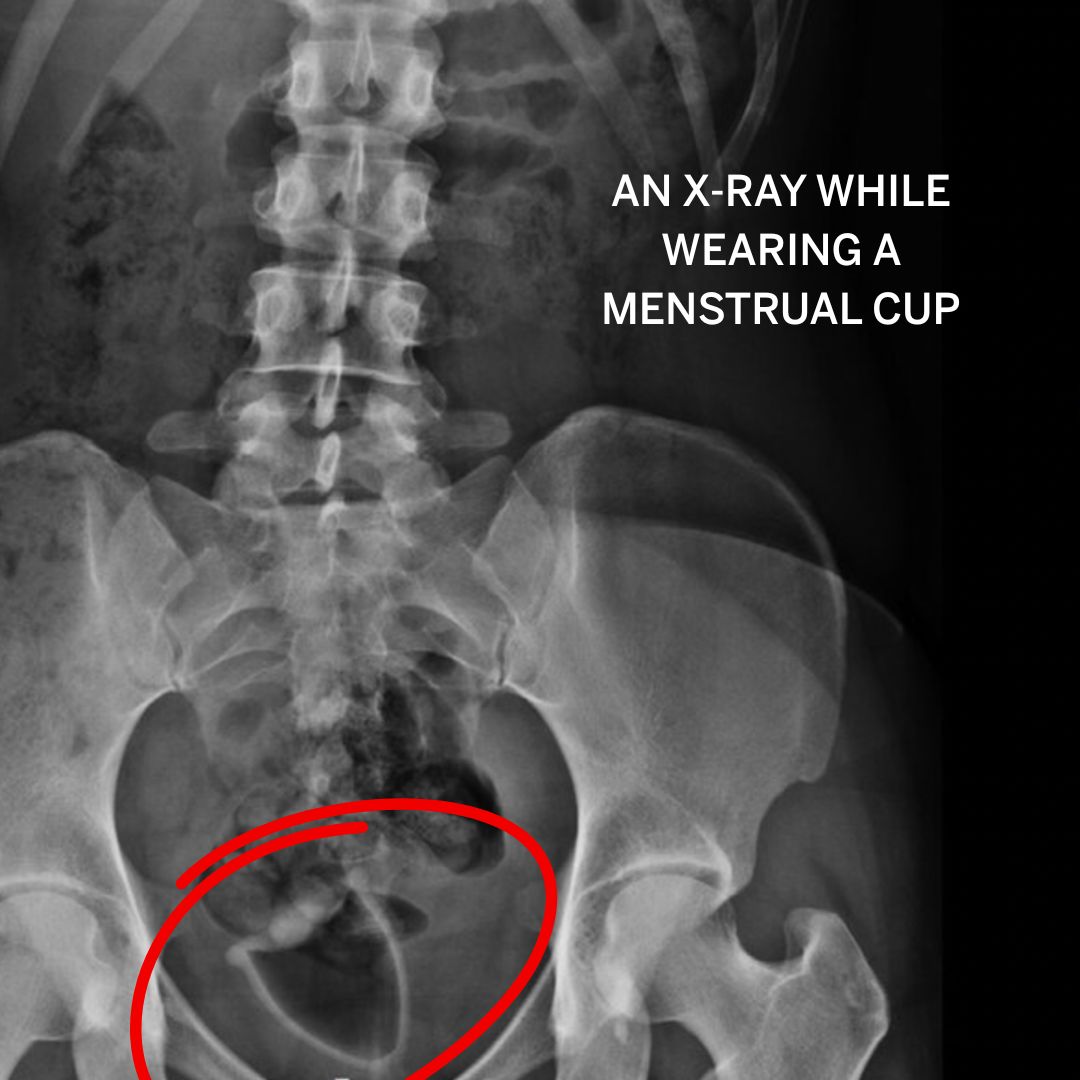

I got to thinking...how does a menstrual cup actually sit in the vaginal canal? Like, realistically, not just on an anatomy model. Well, I scrolled across this image and found out that tampons and menstrual cups show up on an X-ray!